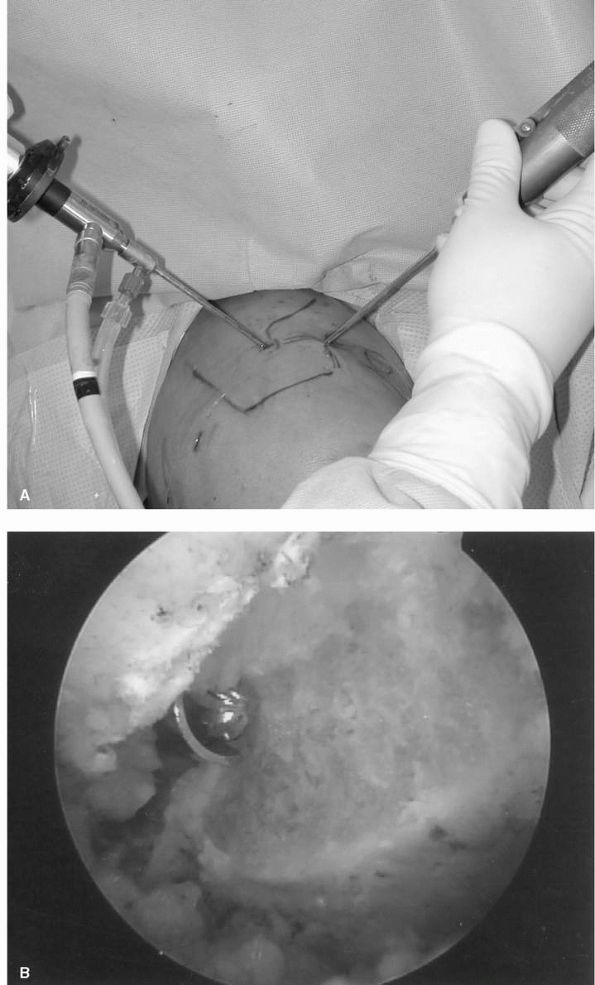

![]() |

FIGURE 12-6. (A) and (B)

Intraoperative photographs of glenohumeral arthritis with flattening of the head, loss of articular cartilage, eburnation of the subchondral bone, and large peripheral osteophytes. |

share similar roentgenographic features. Plain radiographs in the AP

and axillary planes are usually sufficient to evaluate the extent of

disease. The absence of articular cartilage manifests as a loss of the

joint space along with sclerosis of the subchondral bone and

subarticular cysts in both the humerus and glenoid. Flattening of the

humeral head and large peripheral osteophyte formation, particularly

along the anterior and inferior margins, results in an apparent

increase in the head diameter. Although rotator cuff tears are uncommon

in primary osteoarthritis, as previously mentioned, maintenance of the

subacromial space provides a simple initial indicator of rotator cuff

integrity (Figure 12-7).